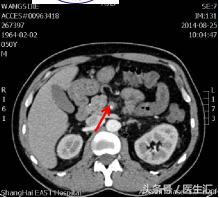

第7天凌晨2:00夜班医生查体全腹部平软,但是上腹部有一点点轻压痛,无反跳痛,麦氏点无压痛,夜班医师给与654-2解痉处理,但是效果还是不满意。所以做了一个中上腹CT平扫示:肠系膜上动、静脉周围渗出性改变,建议增强扫描。第7天早上10:00做中上腹增强CT示:肠系膜上动脉内低密度影,斟酌附壁血栓形成,局部管腔重度狭窄。这个时候这个患者的诊断应该来说已经很明确了。于是请了相关科室的医生进行会诊,决定进行经皮选择性肠系膜动脉造影+肠系膜动脉溶栓术。患者溶栓导管行脉冲式注射尿激酶溶栓,患者术后24h出现便血4次,200ml/次。